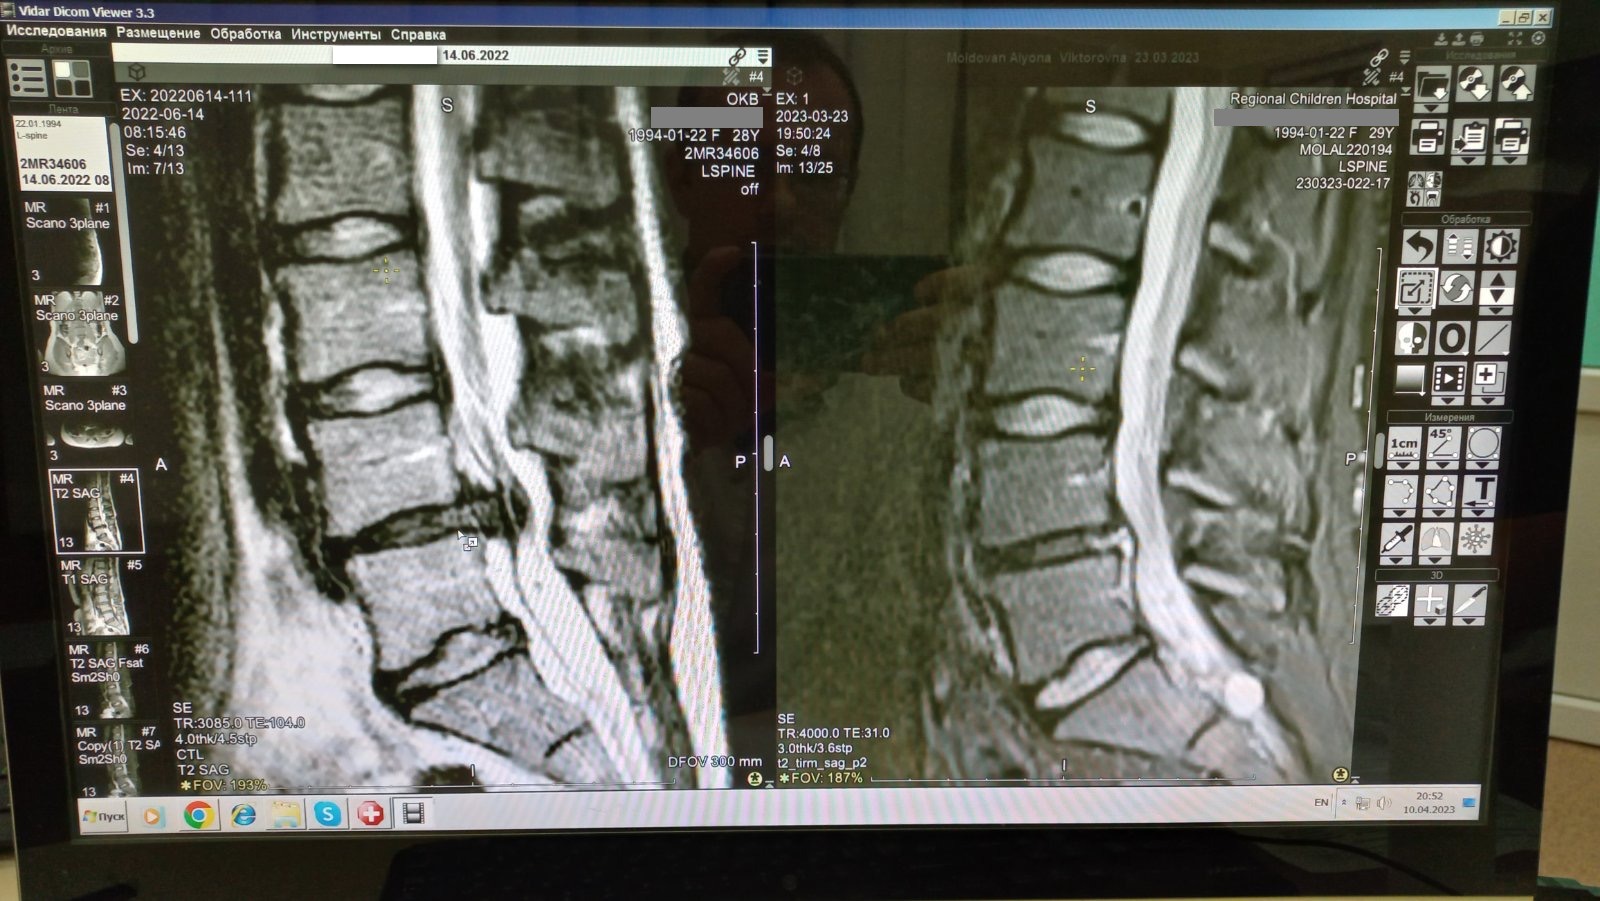

Лечение грыж позвоночника

Грыжа позвоночника - это болезненная деформация позвоночного столба, которая может возникнуть у пациентов разного возраста. Лечение грыж может быть как консервативным, так и хирургическим. В программе "Просто о здоровье" рассказывается о нюансах каждого вида лечения.

Эффективное лечение грыжи межпозвонкового диска без операции

Грыжа межпозвонкового диска (МПД) – наиболее частое следствие дегенеративно-дистрофического процесса в позвоночнике, проявляющееся в самом трудоспособном возрасте болевым синдромом.